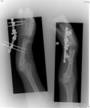

Pre

Op

Xrays